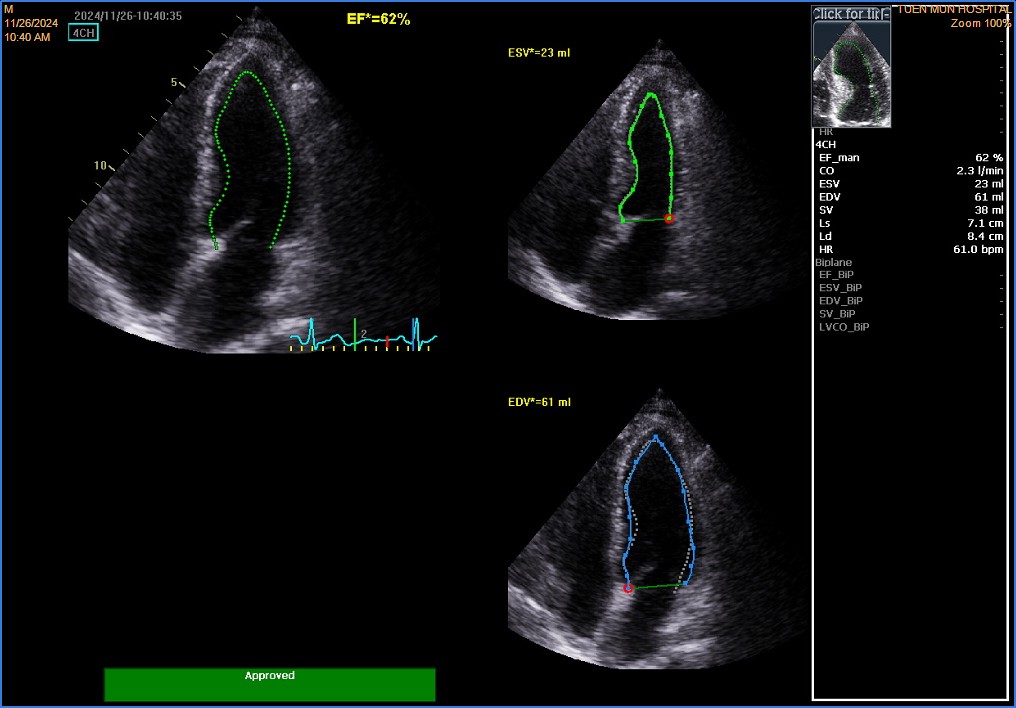

Blood tests were unremarkable. LDLc was 1.7mmol.L.A1c was 6.0. Echo showed normal LV systolic function, with LVEF 65%.Mild hypokinetic mid to apical anterior wall was noted.There was no pericardial effusion.

4ch.avi